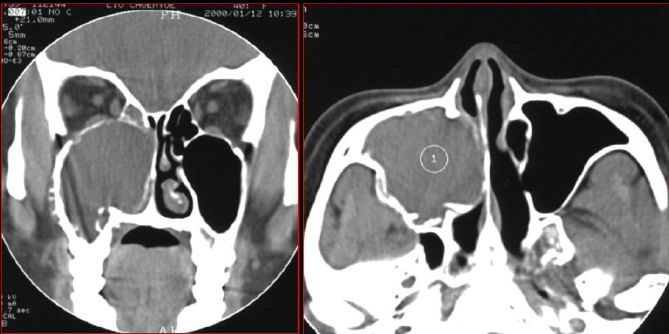

蝶窦炎—眶尖综合症

鼻窦炎—眶尖综合症